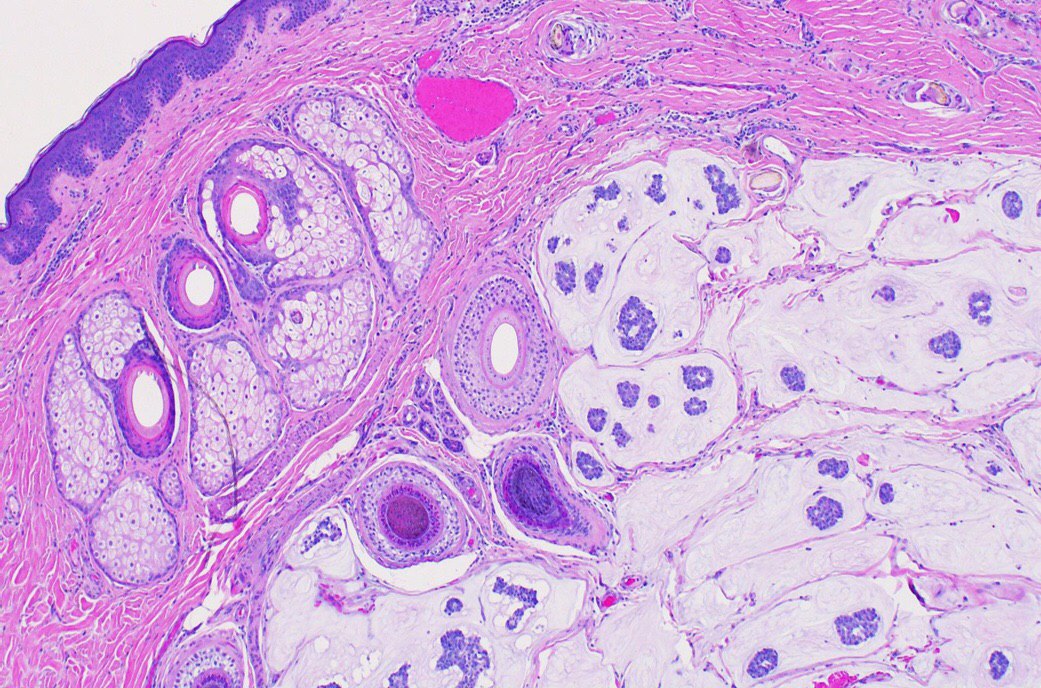

4)В печени, но не печень.... первично желудочная хориокарцинома